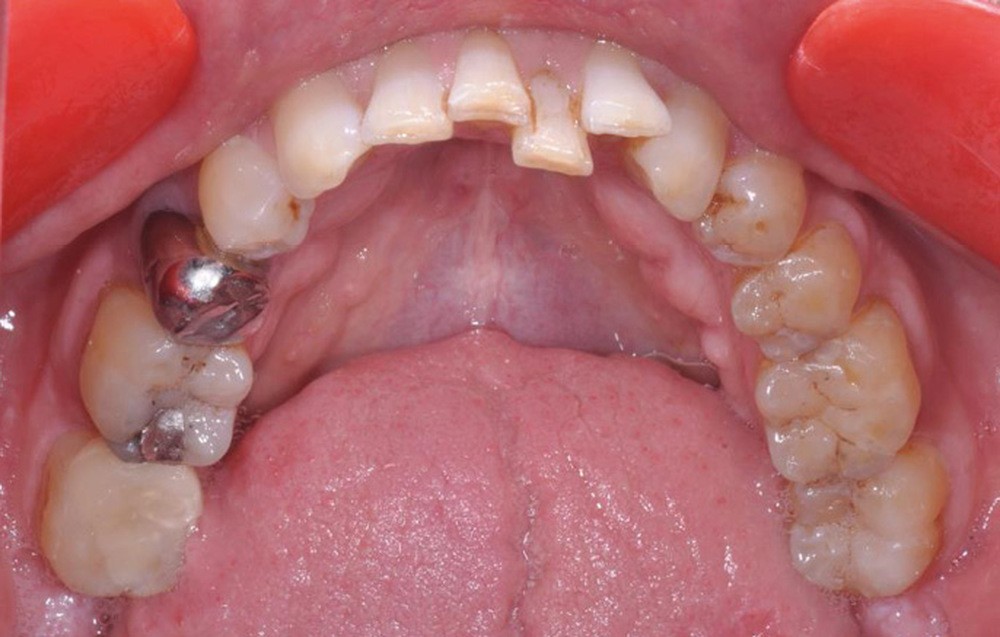

À la radiographie panoramique, on constate une lésion apicale sur 15 et une atteinte inter radiculaire sur 16 ainsi qu’une légère rotation de 21 sans gêne pour le patient.

Plan de traitement

(fig. 4 à 10)

Le plan de traitement établi conjointement avec son chirurgien-dentiste traitant consiste à réaliser un alignement dentaire mandibulaire et à réaliser des extractions de 16 et 15 pour un remplacement par prothèse implanto-portée.